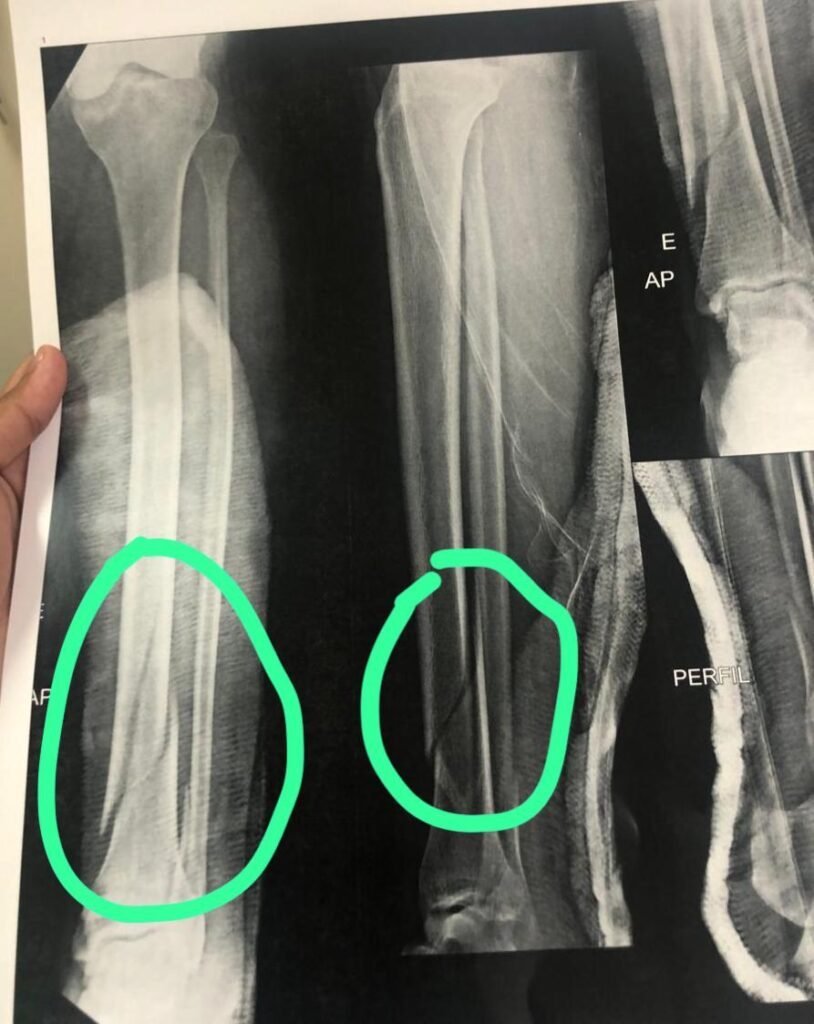

Na manhã de 7 de novembro, uma mãe e seu filho autista caíram em uma cratera na Rua China, bairro Jurema, em Vitória da Conquista. A mulher foi socorrida pelo SAMU e está internada, aguardando uma cirurgia de emergência. Moradores relatam que já pediram inúmeras vezes à prefeitura uma solução definitiva, mas até agora a única medida tomada foi cobrir o buraco com areia, que foi levada pela chuva. A comunidade continua a pedir por uma resposta rápida e efetiva para evitar novos acidentes.